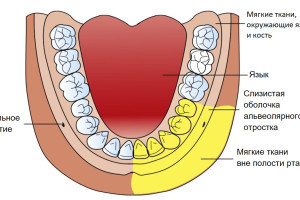

Сенсорная иннервация верхней челюсти обеспечивается второй ветвью тройничного нерва - верхнечелюстным нервом. Эта ветвь покидает полость черепа через круглое отверстие, достигает крылонебной ямки и проходит сквозь нее, как подглазничный нерв, отдавая множество ветвей. Что касается местной анестезии на верхней челюсти, важны следующие ветви:

- Большие и малые небные нервы

- Задние, средние и передние верхние альвеолярные нервы

- Подглазничный нерв (Рис.1)

Рисунок 1. Ход верхнечелюстного нерва и его главных ветвей.